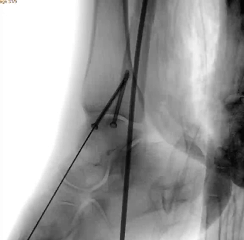

通过 5 毫米小切口将关节镜探入关节腔内,清理腔内淤血与致炎因子,清晰观察骨折块移位及关节软骨损伤情况;

在关节镜直视下,使用微创器械将骨折块复位至解剖位置,恢复关节面平整;

依托机器人导航系统,规划螺钉置入通道,避开关节面与重要组织;

最后通过另外两个 5 毫米的小孔置入空心螺钉,完成骨折端的稳定固定。